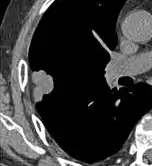

Low attenuating nodule (in this case a fat containing hamartoma).[9]

Cavitation with relatively thick wall, in this case aspergilloma).[9]